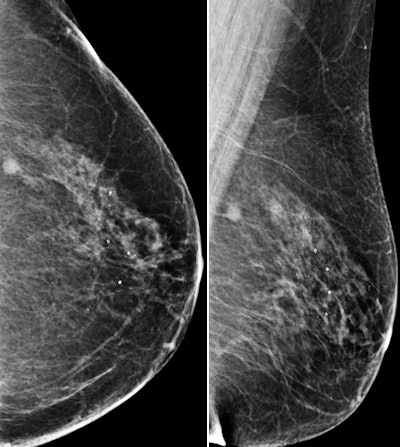

Images are of a 69-year-old postmenopausal woman who had mammographic screening. Screening mammograms (left craniocaudal and left mediolateral oblique views, respectively) show a mass with ill-defined margins in the posterior third of the left breast at 1 o'clock position. All images courtesy of RSNA.

Images are of a 69-year-old postmenopausal woman who had mammographic screening. Screening mammograms (left craniocaudal and left mediolateral oblique views, respectively) show a mass with ill-defined margins in the posterior third of the left breast at 1 o'clock position. All images courtesy of RSNA. B-mode ultrasound scan shows hypoechoic mass with ill-defined margins in left breast at 1 o'clock position.